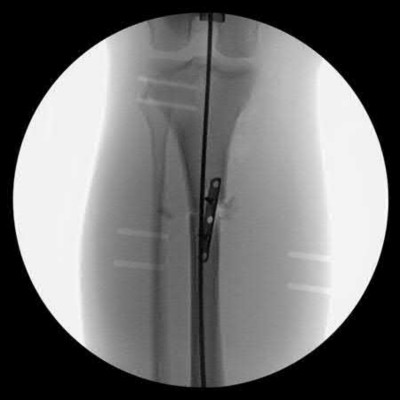

Question 38:

In the treatment of unstable intertrochanteric femur fractures with a cephalomedullary nail, achieving correct lag screw placement is critical. According to the original study by Baumgaertner et al., what is the ideal tip-apex distance (TAD) recommended to minimize the risk of lag screw cut-out?

Options:

- Less than 10 mm

- Less than 15 mm

- Less than 25 mm

- Less than 35 mm

- Greater than 25 mm

Correct Answer: Less than 25 mm

Explanation:

Baumgaertner et al. defined the tip-apex distance (TAD) as the sum of the distance from the tip of the lag screw to the apex of the femoral head on both AP and lateral radiographs, after correcting for magnification. A TAD of less than 25 mm was shown to significantly correlate with a minimal risk of lag screw cut-out in the treatment of intertrochanteric fractures.